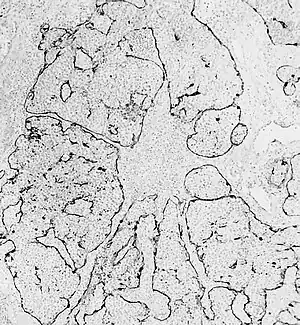

Pathophysiology

Esthesioneuroblastoma is of neurocrest origin, arising from olfactory sensory cells in the olfactory epithelium.[1] The olfactory epithelium consists of olfactory sensory cells, sustentacular cells and basal cells.[1] Esthesioneuroblastoma consists of lobular sheets with neurofibrullar fibers and rosettes.[4] Hyam's classifications are an important way of determining prognosis.[10]

Esthesioneuroblastoma can resemble small blue cell tumors like squamous cell carcinoma, sinonasal undifferentiated carcinoma, extranodal NK/T cell lymphoma, nasal type, rhabdomyosarcoma, Ewing/PNET, mucosal malignant melanoma and neuroendocrine carcinomas (NEC) that occur in the intranasal tract.[1] Compared to other tumors in the region, esthesioneuroblastoma has the best prognosis, with an overall five-year survival rate of 60–80%.[1] Fewer than 700 cases have been documented in the United States alone.[12] Esthesioneuroblastoma is characterized by neurofibrillary stroma and neurosecretary granules that are not seen concurrently by any other pathologies in the region.[1] Histological tests such as keratin, CK5/6, S-100 protein or NSE can be run to further differentiate esthesioneuroblastoma from other tumors.[1]